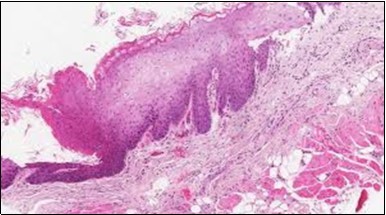

Figure 5.HCL: hairy cells with infiltration in the spleen(21).

Figure 11.HCL Oral mucosa with soft tissue infiltration of hairy cells(27).